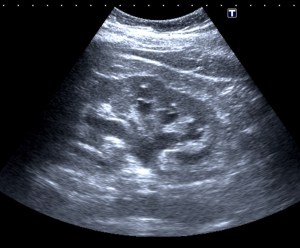

Tras el tratamiento de la recidiva y nefrostomía para la hidroureteronefrosis, vuelve acudir al hospital a los 9 meses por episodio de dolor en FD y malestar general. Se realiza una ecografía de urgencias.

Se realiza nueva TC bifásico abdominopélvio y Uro TC.